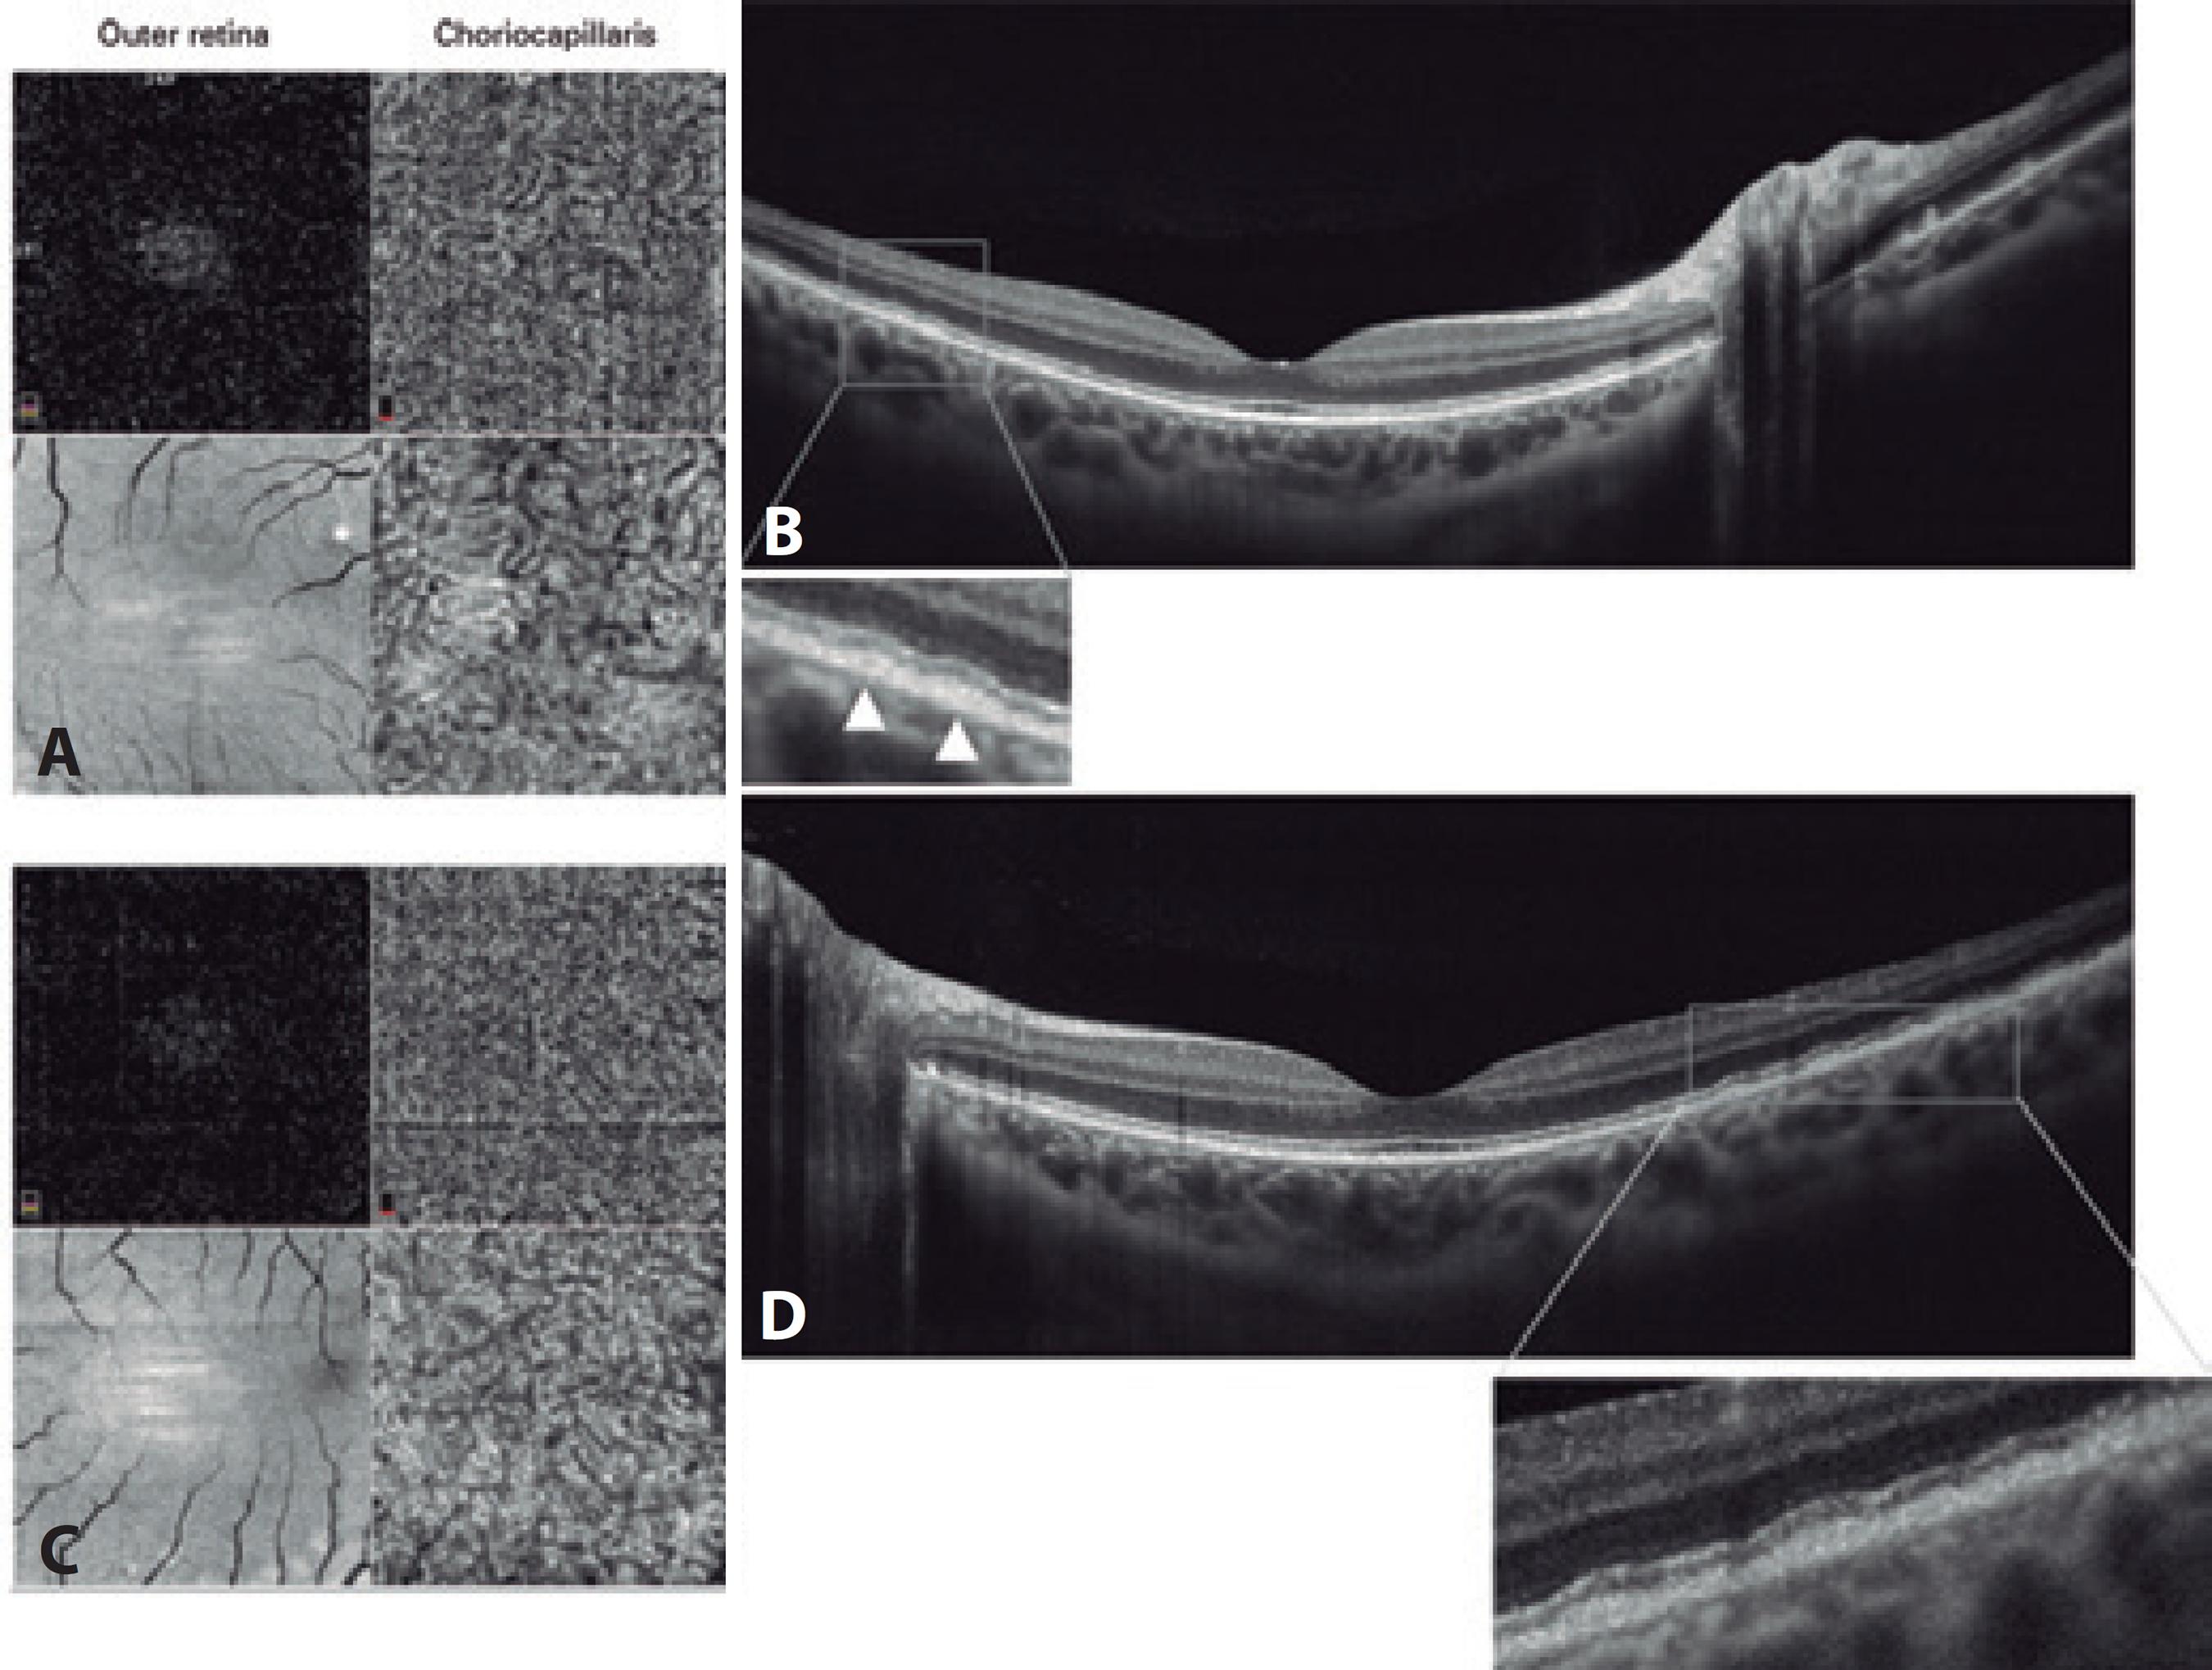

Increased autofluorescence corresponding to retinal flecks was observed in the infrared image (Figure 2). Fluorescein angiography showed a healthy macula with hypofluorescent spots related to pigment clumps; these extended to the far periphery but without macular injury. ERGs were recorded under scotopic and photopic conditions and were normal except for the selective reduced amplitude of oscillatory potentials (Figure 3). Electrooculograms revealed light peak/dark trough ratios (Arden ratios) of 1.9 in the right eye and 2.0 in the left eye (Figure 3). The patient’s macula was tested with a spectral domain (SD) optical coherence tomography (OCT) B-scan and SD-OCT angiography, using an Avanti RTVue XR with AngioVue® software (Optovue, Inc., Fremont, CA). The imaging data were obtained using split-spectrum amplitude-decorrelation angiography software. The testing demonstrated a normal foveal structure with increased thickness of the RPE in both eyes. The 3 × 3 mm SD-OCT angiography showed no macular injury from the outer retina to the choriocapillaris slab in both eyes. Projection artifacts were removed using a default proprietary algorithm (Figure 4). At a follow-up examination 18 months later, the patient continued to have no ocular symptoms.

Figure 4 Optical coherence tomography (OCT) angiography with a split-spectrum amplitude decorrelation algorithm and structural en face OCT 3 × 3 mm (A and C), which showed no macular injury from the outer retina to the level of choroid capillary in both eyes. The OCT B-scan (B and D) demonstrated a slight increase in the thickness of the retinal pigment epithelium, leading to multiple small pigmented epithelium detachments. The enlarged images of the boxed regions show the outer retina and retinal pigment epithelium of both eyes in detail. The hyperreflective band corresponding to the photoreceptor inner/outer segment junction remained intact in both eyes.